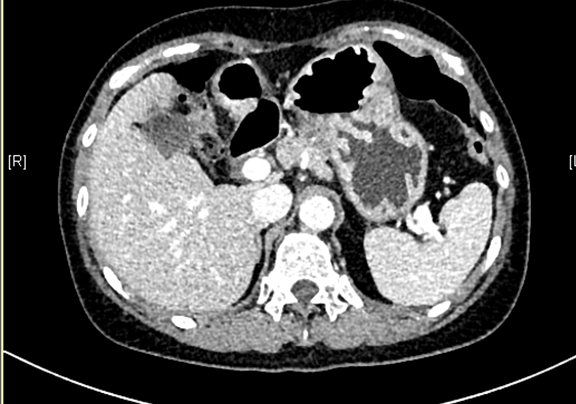

下腹部增强CT示:肝左外叶肝癌可能性大; 肝左内叶及右后叶海绵状血管瘤可能性大。

术前CT检查:

动脉期

将0.625mm双源薄层CT资料的静脉期和动脉期Dicom格式文件导入海信CAS系统。

通过调节窗宽窗位调整CT序号,对肿瘤,肝实质,胆囊,下腔静脉,肿瘤,肝动脉、门静脉及肝静脉等进行三维重建;系统自动计算肿瘤体积和肝脏体积。